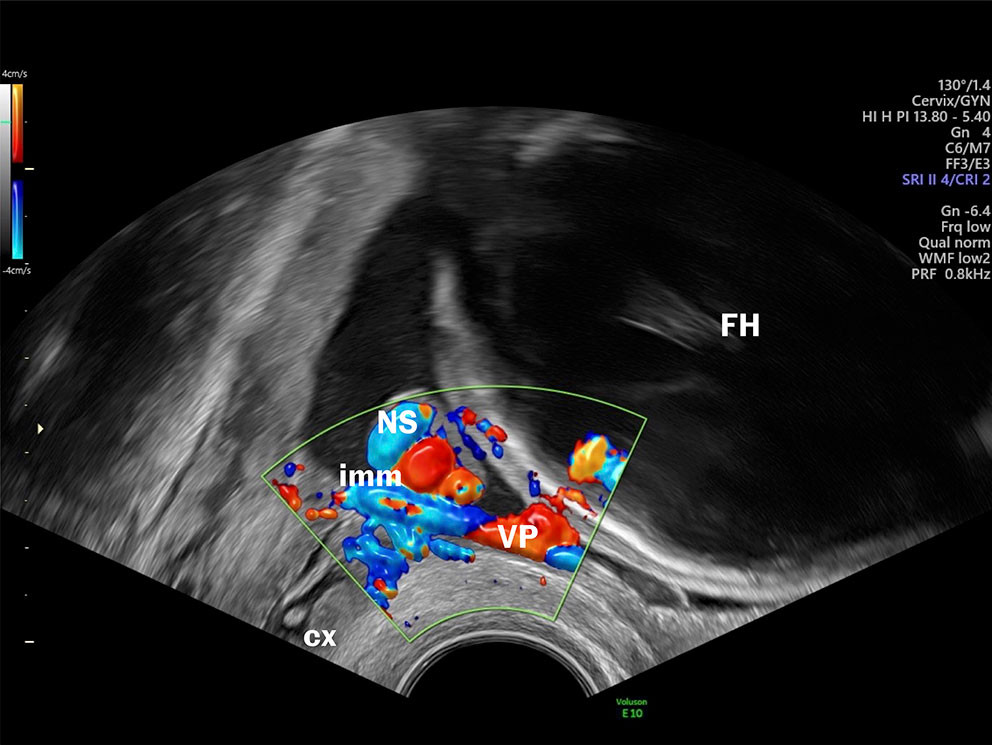

Selv om man har kjent til muligheten for å diagnostisere vasa previa og velamentøse blodårer med ultralyd siden sent på 1980-tallet, inngår det ikke å avkrefte eller bekrefte vasa previa i rutineundersøkelsen i Norge. Transvaginal ultralyd har høy sensitivitet og spesifisitet med hensyn til å diagnostisere vasa previa (13), og falskt positive og falskt negative funn forekommer sjelden. I tillegg er undersøkelsen billig, medfører lite ubehag for kvinnen, ingen risiko for fosteret og er rask å utføre (få minutter) (figur 1) (se video).

Velamentøse blodårer er assosiert med risiko for uønskede utfall for både mor og barn (5–8). I noen prosent av tilfellene løper de ubeskyttede føtale blodårene i hinnene foran indre mormunn. Da kalles tilstanden vasa previa. Når vasa previa er diagnostisert, er målet å forløse kvinnen med keisersnitt før spontan vannavgang eller ruptur av hinnene. Foster til termin har et blodvolum på ca. 3–4 dL (110 ml/kg) og det har ikke gode kompensasjonsmekanismer hvis det oppstår blødning. I løpet av sekunder kan blødning fra et velamentøst kar nå et volum som får fatale konsekvenser (9). Ikke uventet er derfor dødeligheten ved uerkjent vasa previa høy, opptil 56 %, og om barnet overlever, er det høy risiko for alvorlig sykelighet (10). Men dersom tilstanden er kjent før fødsel, er overlevelsen nesten 100 % og med normale utfall på kort og lengre sikt (11).